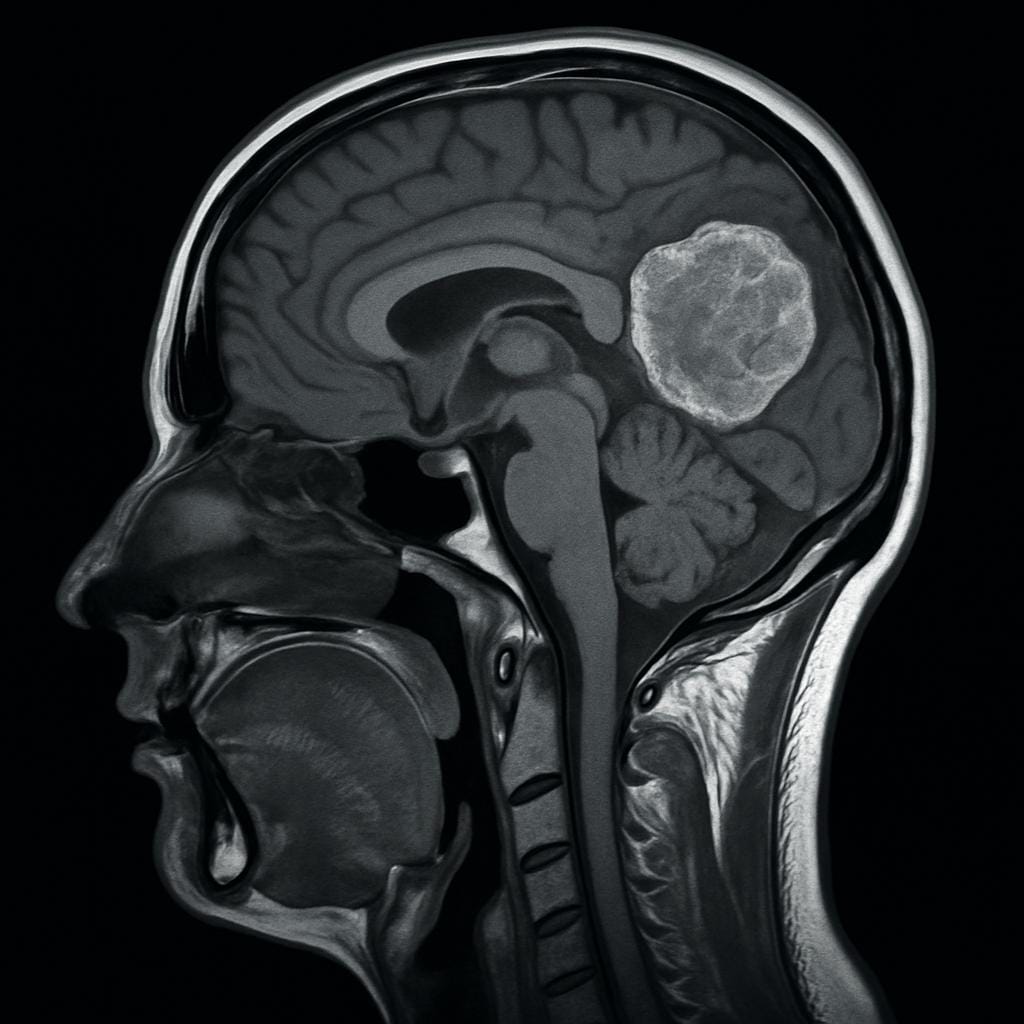

Descubra os principais sinais de alerta dos tumores cerebrais, como dor de cabeça persistente, convulsões e alterações de comportamento. Diagnóstico precoce pode salvar vidas.

Tumores cerebrais são formações anormais de células dentro do crânio. Eles podem ser benignos (não cancerosos) ou malignos (cancerosos), e afetam o cérebro ou a medula espinhal. Mesmo os tumores benignos podem causar sintomas graves por pressionarem estruturas delicadas.